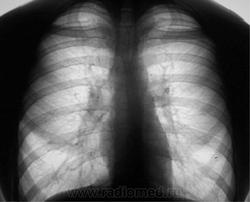

Да, все оказалось, как нельзя лучше, была признана норма. Это призывник, был призван, в армию дважды проходил флюорографию, занимался в армии спортом, и как положено в срок был уволен, но решил себя посвятить работе в УВД.

При прохождении комиссии в поликлинике УВД жалоб не предъявляет. Профилактическая цифровая флюорография органов грудной полости (по месту жительства) - патологических изменений не выявлено. Но терапевта смутила, уж сильная "стройность" юноши, и он был направлен "на всякий случай" на рентгенографию ОГК.

Таковая ОГК, и была произведена.

Какие мнения будут уважаемые коллеги?